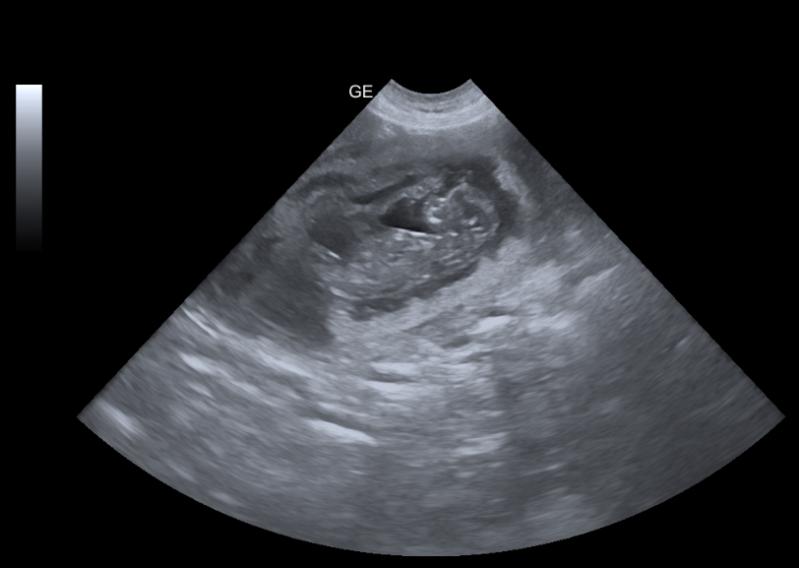

Um sicherzustellen, dass es Lucy gut geht und Sie wirklich nicht tragend ist, gab es einen Kontrollultraschall.

Und mein Bauchgefühl täuschte mich nicht. Lucy ist Tragend :)

Die Babys zeigten sich mit aktivem Herzschlag. Eine Einschätzung zur Anzahl der Welpen konnte nicht abgegeben werden. Daher entschieden wir uns zum Röngten. Voller Spannung kam der Röngtentermin. Aber Lucy wollte einfach nicht verraten, was in ihr heranwächst. Wir wussten nun aber anhand der Größe der Babys, das Lucy verzögert aufgenommen hat. Naja die Natur lässt sich nicht beeinflussen.